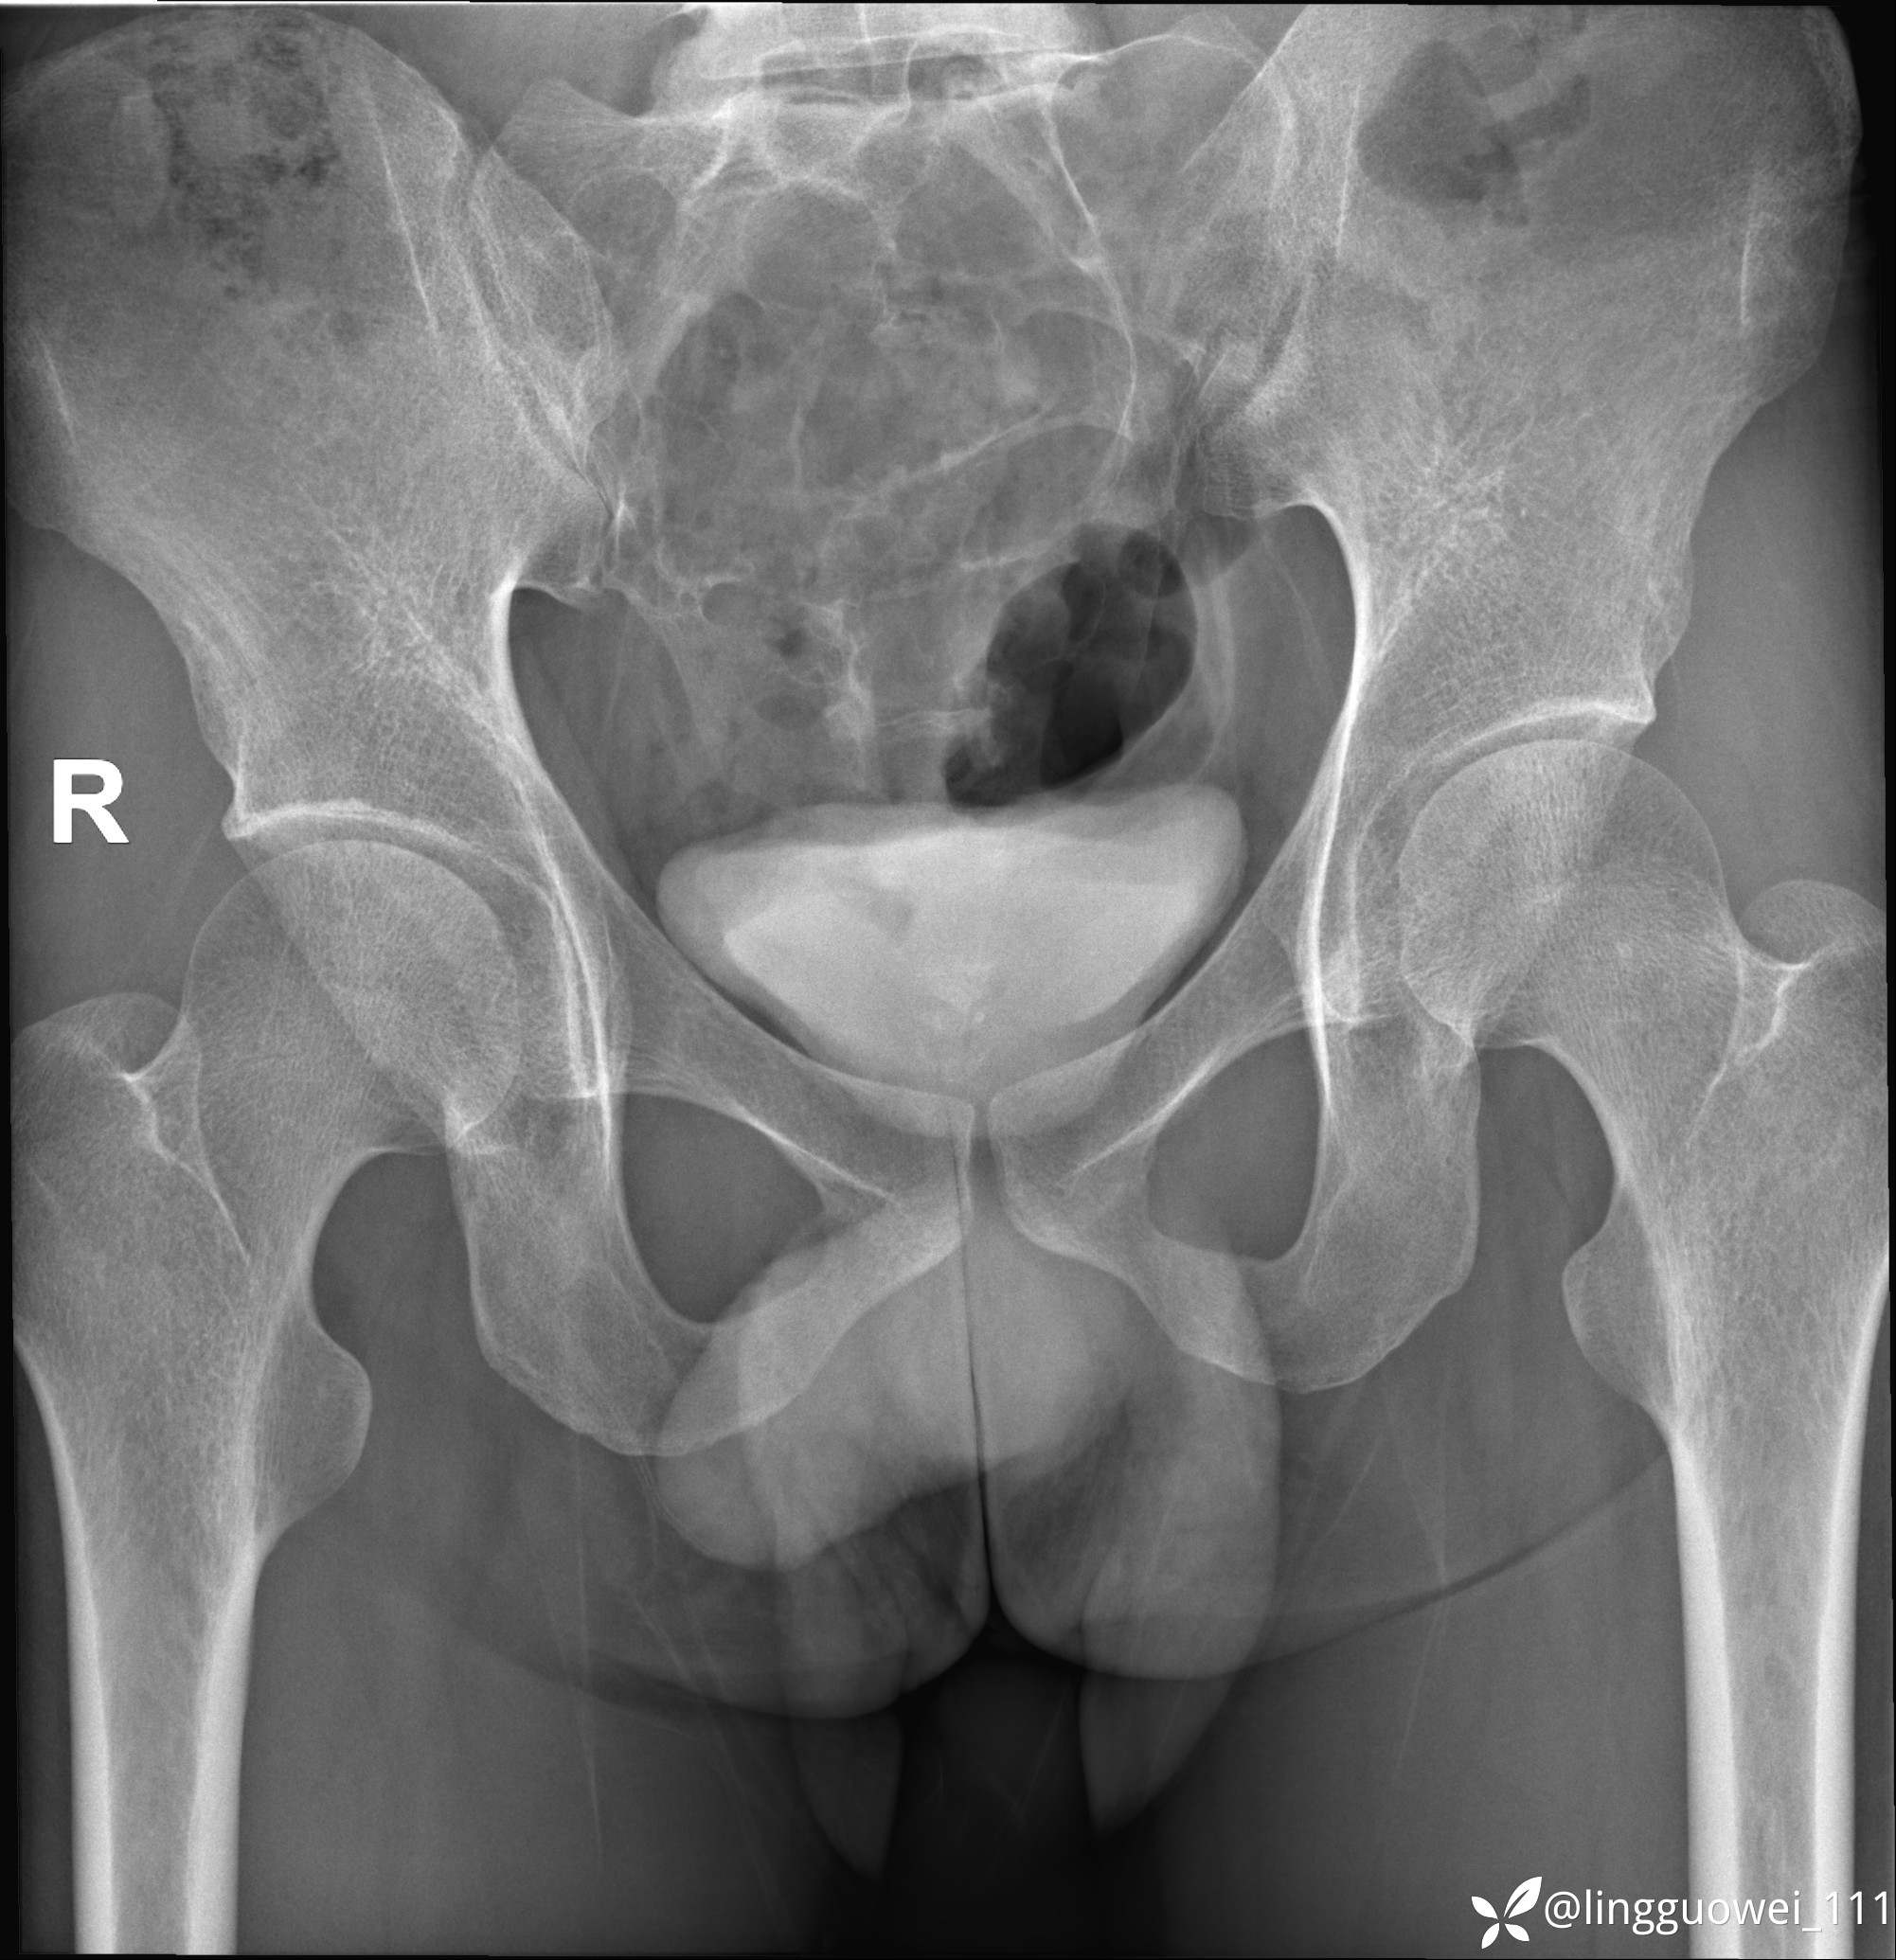

男,25岁,腰痛4年,加重左下肢痛5天,先上传X光片,第2天再上传CT。MR

img